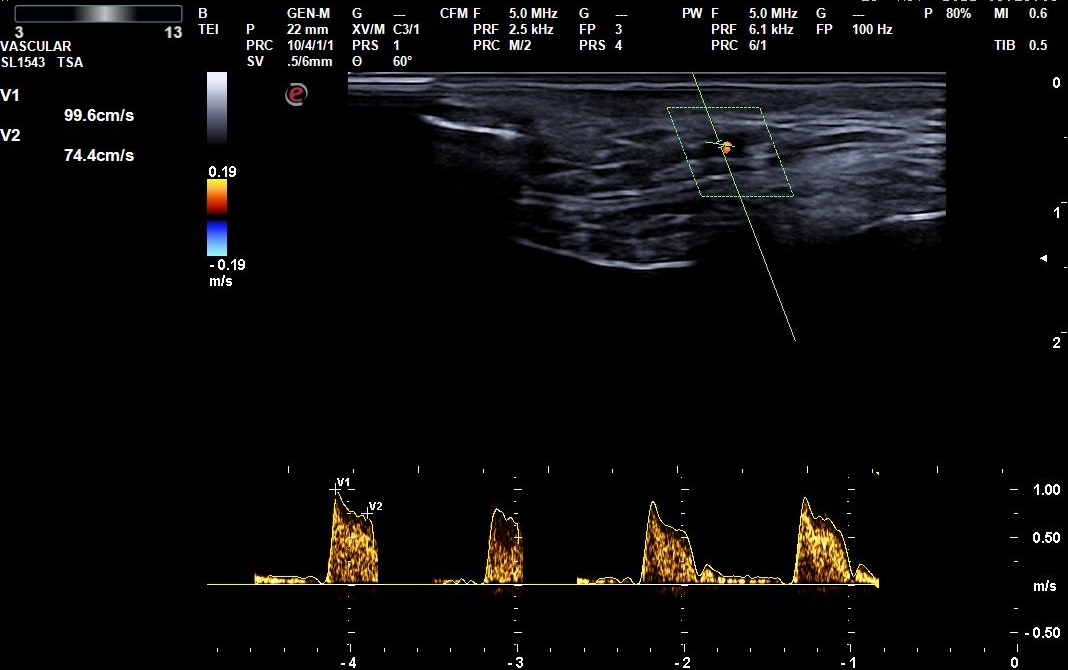

Descripción de los hallazgos ecográficos y las imágenes más relevantes para la resolución del caso

Signo del halo de manera parcheada. Se completa con realización de Doppler de las arterias temporales en ambos lados, observándose en porciones distales en el vaso una hipodensidad sin relleno y disminución del flujo compatible con inflamación del vaso. En tramos proximales se observa buen relleno vascular y flujo sin alteraciones. Todos estos hallazgos con compatibles con alta sospecha de arteritis de la temporal principalmente en sus tramos distales.